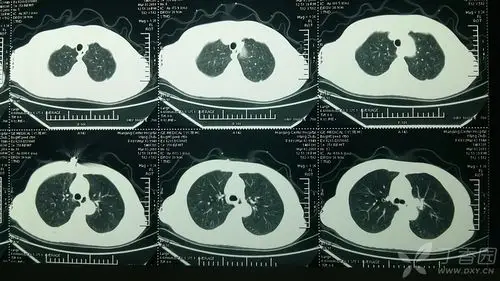

【读片】肺癌? [病例帖]

这个肺部肿瘤藏得深,胸片分分钟漏诊,追踪下来该来的都来了 [病例帖]

肺结核? [病例帖]

请问这个69岁女性ct扫描结果肺癌风险多大?

【读片】右肺上叶中央型肺癌,前纵隔囊性密度影是什么结构 [病例帖]